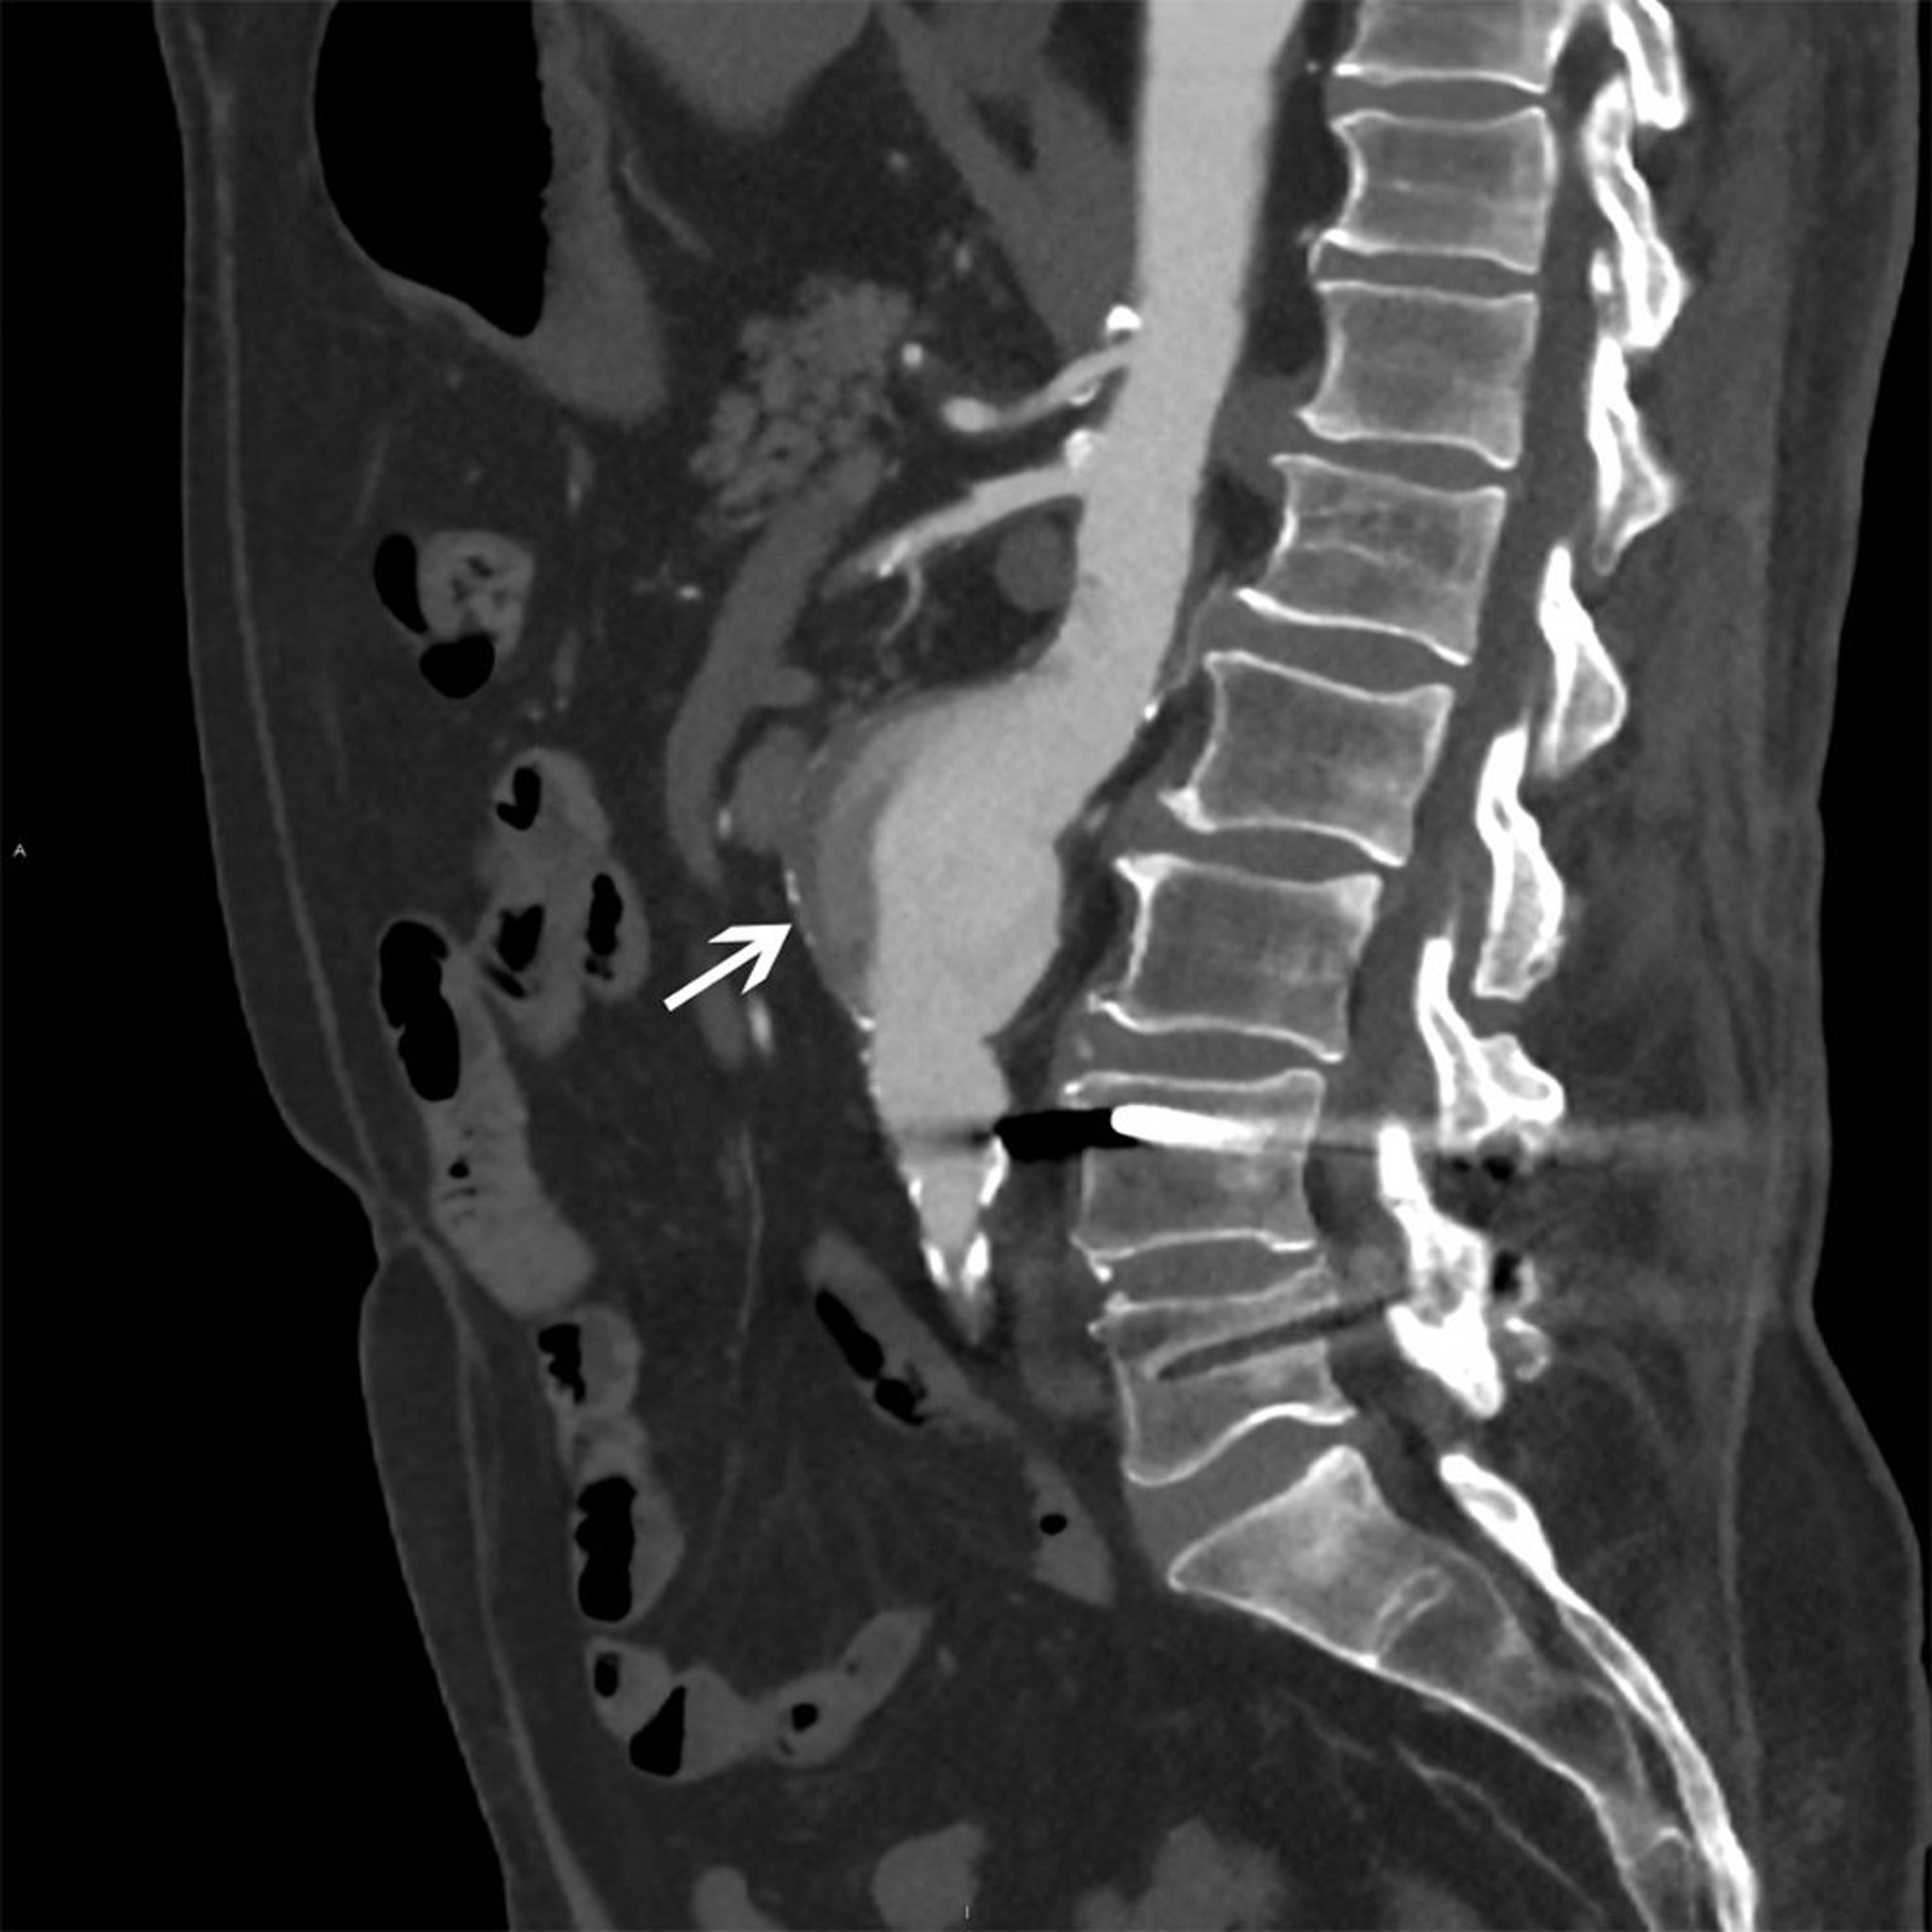

Аневризма брюшного отдела аорты (КТ-сканирование)

Белая стрелка показывает аневризму брюшной аорты размером 5 см с неоднородным потоком и пристеночной бляшкой.